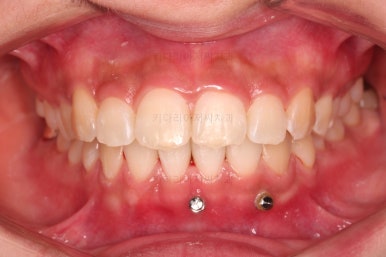

우선 윗니 앞니는 장치를 부착했고요.

아래 앞니는 장치 부착 이전에 아래로 앞니를 내려줄 미니스크류를 식립했습니다.

미니스크류가 단단하게 붙었을 시점에 아래 앞니도 장치를 부착하고요.

과개교합 개선을 위해서 미니스크류까지 힘을 줘서 아래 앞니를 내려줍니다.

이번 환자분이 사용한 장치는 엠파워 클리어라고 하는 자가결찰 세라믹 장치입니다.

아래 앞니는 브라켓보다는 훨씬 작은 미니튜브 장치를 사용했습니다.

과개교합의 경우 브라켓을 부착하게 되면 씹히게 되어 치료과정이 수월하지 못하기 때문이죠.

장치 부착 시점의 장치가 보이는 모습과 입매 변화 관찰해 주시고요.